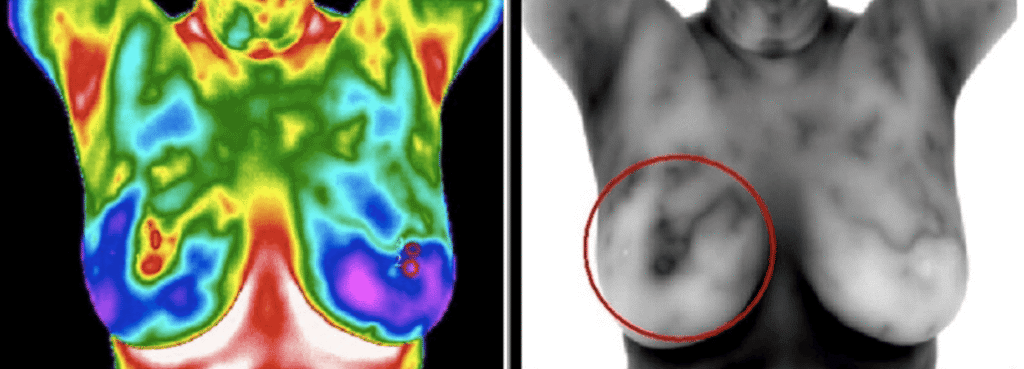

Patricia Bowden-Luccardi: Thermography looks at heat, not organ systems. It looks at the surface heat on the skin for markers of inflammation. So, for example, thermography can see the inflammation from a tumor sometimes as early as 7-10 years before it can be seen on a mammogram, an MRI or an ultrasound. Thermography can also detect lack of heat as well as lymphatic patterns that can indicate things like blockages or lymphatic backup which are important to notice.

The biggest thing in my practice that I’ve been doing for 13 years is working with estrogen dominance. My patients go on sulforaphane and take it every day for six months. We see huge results in the elimination of estrogen dominance. And, what’s cool is that you can actually see this visually on the thermography scan–it commonly looks like leopard spots or pockets of inflammation.

Sulforaphane is my favorite nutraceutical that I work with in my practice, and this is where I’m getting the most results with estrogen dominance. And, because we can see the results visually on the scan, it’s very satisfying that we know we’re moving in the right direction and essentially reversing the potential onset of breast cancer.